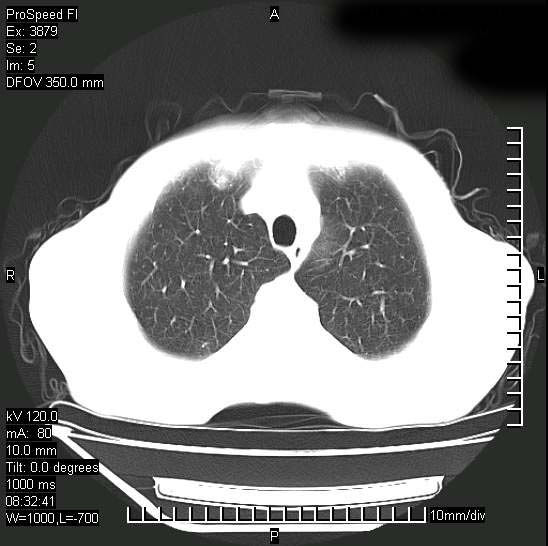

以下是引用37度在2008-6-6 11:20:00的发言:[br]1.包裹性积液,多考虑结核性;[br]2.穿刺术后改变。

以下是引用312nanyang在2008-6-6 15:12:00的发言:[br]基本支持楼主意见[br]疑问?左下肺支气管旁的软组织(16层)密度怎么解释?淋巴结还是斜裂胸膜增厚所致?能否增强进一步检查